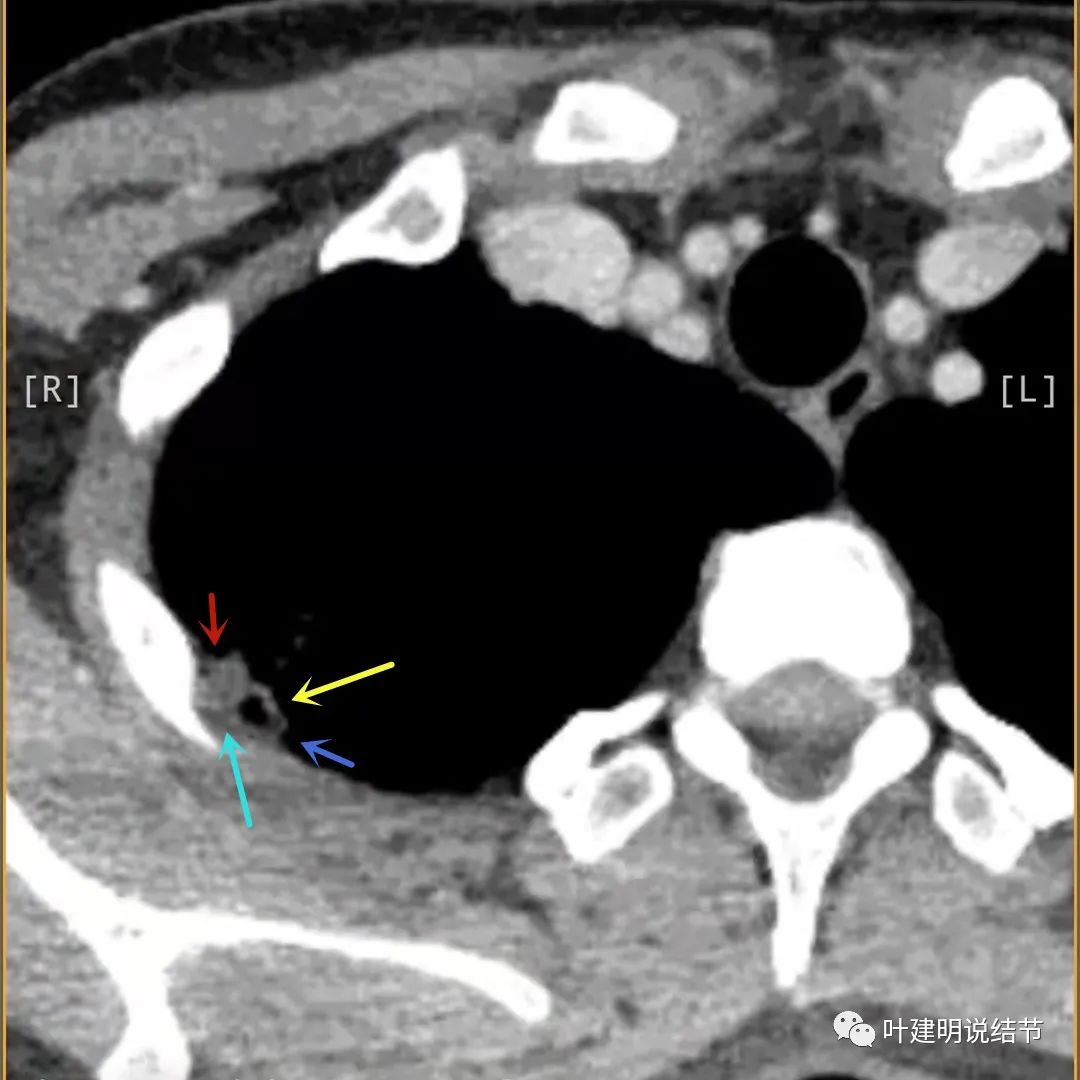

病灶有明显强化(说明炎性可能性大,如果恶性这样强化,血供丰富,应该倍增速度更快。蓝色箭头示胸膜处低于软组织密度的区域;桔色箭头示病灶边缘平直缺乏膨胀性;黄色箭头示中间的空腔

天蓝色箭头示病灶低密度区,考虑坏死可能性大,桔色箭头示边缘凹陷无膨胀性

上图示空洞偏心,而且红色箭头所指处与空腔似乎是整合,而非囊壁生长增厚。天蓝色箭头示近胸膜处的低密度区域,考虑坏死成分,囊壁的邻近部分也是极低密度区域,也可能是干酪样坏死区